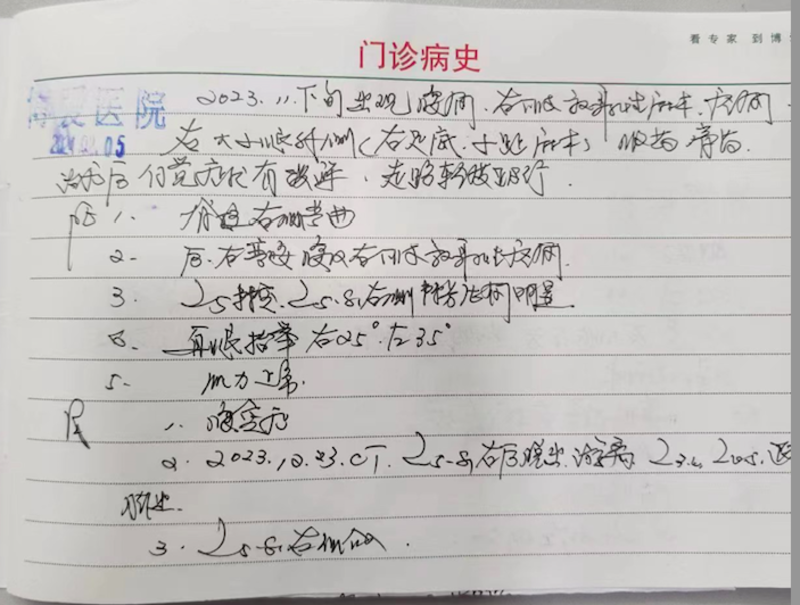

患者 (保护隐私隐去姓名)男 38岁

2024年2月5日前来面诊,

主述:腰痛,右下肢放射性疼痛约三个月

病史:2023年11月下旬出现腰痛,右下肢大小腿外侧放射性疼痛,麻木涉及右足底,1-5脚小趾。,服药,膏药治疗后自觉症状有缓解。走路轻度跛行。

体检:

1:脊柱右侧弯曲

2: 后、右弯腰时腰及右下肢放射性疼痛

3:L5棘突,L5.S1右侧棘旁压痛明显

4:直腿抬举右侧25度,左侧35度

5:双侧肌力正常

诊断:

1, 腰突症

2, 2023.12.23腰椎CT;L5.S1右后脱出游离。L3.4,L4.5椎间盘退变,膨出(见图1)

3, L5.S1右侧介入治疗

4, 腰部保健宣教。